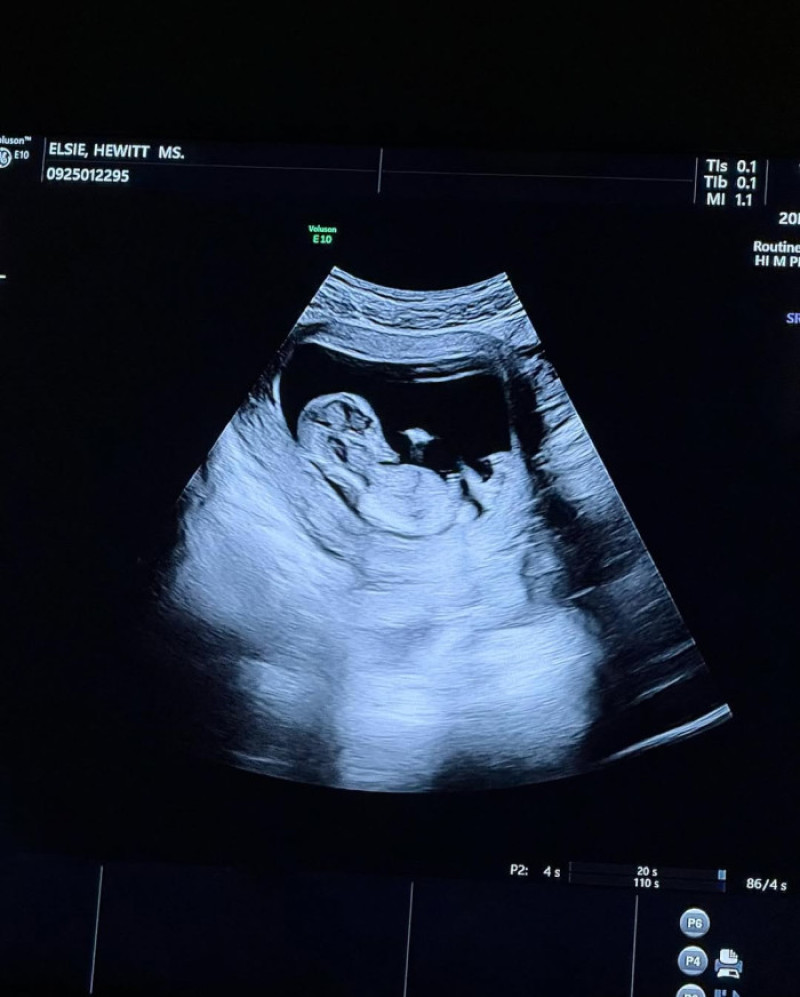

„Sunt foarte fericiți împreună și le merge de minune”, a declarat o sursă pentru People. În urmă cu doar câteva zile, Elsie a anunțat sarcina pe Instagram, alături de imagini cu ecografia și o fotografie amuzantă cu Davidson ținându-i burtica, cu mesajul: „Ei bine, acum toată lumea știe că am făcut sex.”

Pete Davidson și Elsie Hewitt/ Foto: Instagram